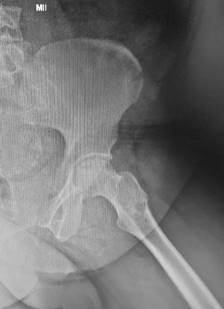

La técnica quirúrgica utilizada fue la perforación o Forage del núcleo cefálico, sobre mesa ortopédica bajo intensificador de imágenes (imagen en dos planos). Se introdujo una aguja guía hasta la zona de osteonecrosis. El orificio de inicio sobre la cortical externa del fémur se realizó a nivel del trocánter menor para evitar fracturas por estrés del fémur. A través de la aguja guía se introdujo una broca canulada de 9 mm de diámetro hasta llegar a 5 mm del cartílago articular (Figura 3). En todos los casos se obtuvo una muestra ósea para biopsia que confirmó el diagnóstico. Para la suplementación con ACMO, se obtuvo la muestra de zona dadora -cresta ilíaca- en forma percutánea, para posterior filtrado con utilización del sistema RegenKit BMC, Stryker, USA (Figuras 4 y 5).

Figura 3: Fresado de canal de descompresión y colocación de suplemento de aspirado de médula ósea.